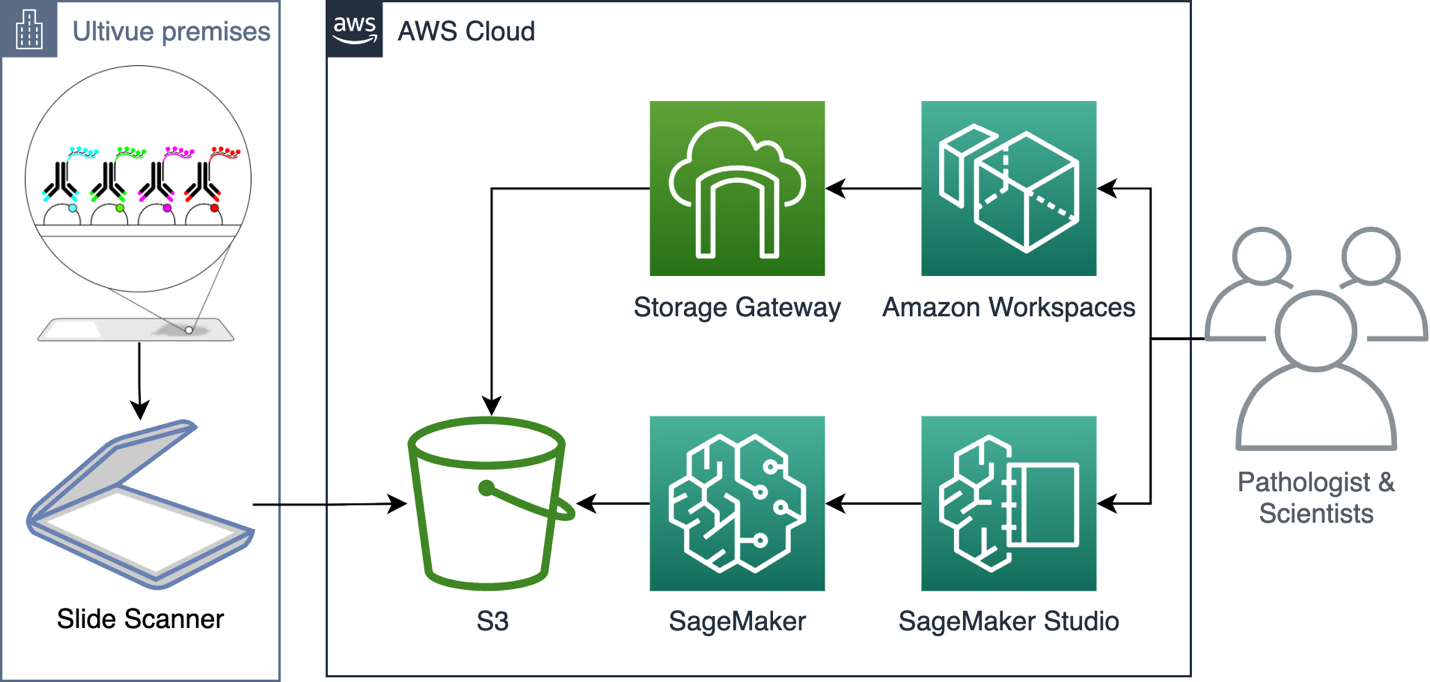

Amazon Simple Storage Service (Amazon S3) provides a cost-effective and scalable solution for storing this data, and in combination with AWS Storage Gateway, traditional block-storage-like access is achievable. AWS Storage Gateway is an important part of our solution, as many of the common tools that pathologists and scientists rely on would cease to function without it. However, these commonly used tools that run on a Windows Desktop do not scale very well. That’s where Amazon SageMaker comes in.

Figure 1. The Ultivue architecture using Amazon S3, AWS Storage Gateway, Amazon SageMaker, and Amazon SageMaker Studio as key components.

For this solution, we use Amazon S3 with Intelligent-Tiering to store data in a cost-effective manner with low-latency access. Storage Gateway provides file shares via the SMB network file system that Windows clients can use. Amazon WorkSpaces provides a pre-configured desktop working environments to our users, including the Storage Gateway-backed network drives.

Amazon SageMaker Studio enables cloud working environments for AI engineers, as well as pathologists. We use Amazon SageMaker’s processing, training, and inference APIs to analyze images at any scale.